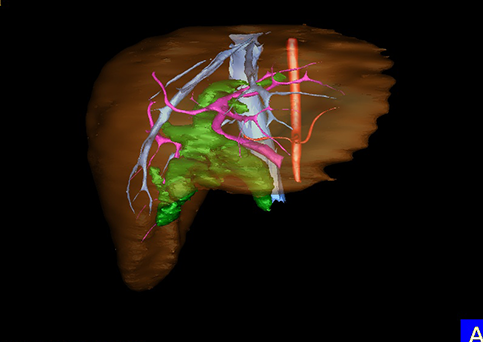

10、三维重建虚拟肝脏、胆道显像技术

三维虚拟肝脏技术是在二维影像学资料如CT等图像的基础上,通过三维重组软件和工具,比如青岛大学附属医院与海信医疗集团联合自主研发的海信计算机辅助手术系统(Hisense Computer Assisted Surgery,Hisense CAS),目前已投入临床并指导实际应用,利用该类系统对二维影像学的数据资料进行三维立体分析,重组形成立体的、有空间结构的、虚拟的肝脏三维图像。这项技术较传统的二维平面成像技术,有着明显的优势,3D虚拟肝脏技术可以构造出一个虚拟的、可视化的肝脏模型。通过对这种模型的观察,可以很容易地分辨出肝脏器官的组织结构、解剖特点,直观研究肝外胆总管的形态差异,明确肝内胆管的形态、走形、是否合并扩张、狭窄及结石,胰胆管合流的形态及共同通道内是否有狭窄、扩张和结石等病变情况,预先规划处理可能合并存在的肝内胆管扩张、狭窄或其他复杂胆道畸形,清晰地显示肝内脉管系统,包括门静脉、肝动脉及肝静脉的走行、分支,并可多角度、全方位观察病变胆道与其周围重要血管尤其是伴行的门静脉之间的解剖关系,大大提高了外科医师在术前对肝脏内部各管道结构及其变异判断的精确性和可靠性,精准地对病变进行判断和评估,还可根据患者自身的病变特点,制定出合理、个体化的手术方案,最大限度地降低术中和术后并发症发生率,并术中导航实时指导手术,提高手术的精准性和成功率。

图10:先天性胆管扩张症囊肿型三维重建虚拟肝脏、胆道显像

a 图为术前二维CT扫描图像,箭头所示为肝内胆管扩张;b 图为CT经多平面重组技术(MPR)图像后处理所得的重建图像,可显示胆总管明显扩张合并肝内胆管扩张;c 图为MRCP显示胆总管呈囊柱状扩张,直径>1 0 cm,伴肝内胆管扩张;d 图示Hisense CAS三维重建清晰显示肝脏、胆道系统及其与门静脉、肝动脉、肝静脉等之间的空间解剖关系;e 图示Hisense CAS可从任意角度以不同脏器组合显示,明确胆道系统与其伴行的门静脉系统的空间解剖关系;f 图示胆道系统立体形态及与肝脏整体的空间关系,箭头处显示肝内胆管狭窄部位发生于左右肝管汇入肝总管处。术前规划需行肝内胆管扩大成形术。